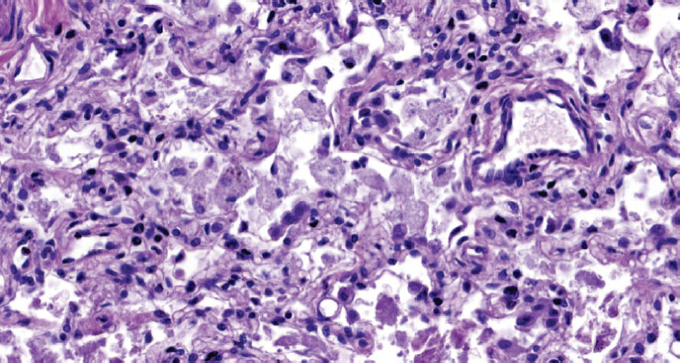

При патологоанатомическом исследовании — ткань легких с диффузными ателектазами, чередующимися с небольшими эмфизематозно расширенными участками, мелкоочаговыми кровоизлияниями в расширенные межальвеолярные перегородки (рис. 1). Большая часть альвеол звездчатой формы, очагово заполнены серозно-фибринозным экссудатом (рис. 2), слущенными альвеолоцитами, альвеолярными макрофагами (рис. 3). Часть альвеол выстлана гиалиновыми мембранами (рис. 4). Сосуды микроциркуляторного русла, расположенные в межальвеолярных перегородках, округлой формы, в просвете большей части которых определяются нити фибрина. Эндотелиальные клетки, выстилающие сосуды, набухшие, овальной формы, другие — более вытянутые, сохраненные не на всем протяжении стенки сосуда. Бронхи среднего и более крупного калибра звездчатой формы, стенка преимущественно утолщена за счет отека и склероза подслизистого слоя. Слизистая оболочка бронхов представлена цилиндрическим эпителием с дистрофическими изменениями, местами слущенным, в сохраненных участках с явлением пролиферации. В просвете бронхиол и более крупных бронхов выявляются десквамированный эпителий, единичные эритроциты, макрофаги. Кроме этого, преимущественно перибронхиально — диффузная лимфоцитарная инфильтрация с примесью умеренного количества нейтрофильных лейкоцитов; разрастание соединительной ткани, образование мелких единичных лимфоидных фолликулов.

Рис. 2. Альвеолы заполнены серозно-фибринозным экссудатом. Окраска гематоксилином и эозином. Ув. ×200 / Fig. 2. The alveoli are filled with serous fibrinous exudate. Stained with hematoxylin and eosin. Magnification ×200

Рис. 3. Альвеолярные макрофаги в просвете альвеол. Окраска гематоксилином и эозином. Ув. ×400 / Fig. 3. Alveolar macrophages in the lumen of the alveoli. Stained with hematoxylin and eosin. Magnification ×400